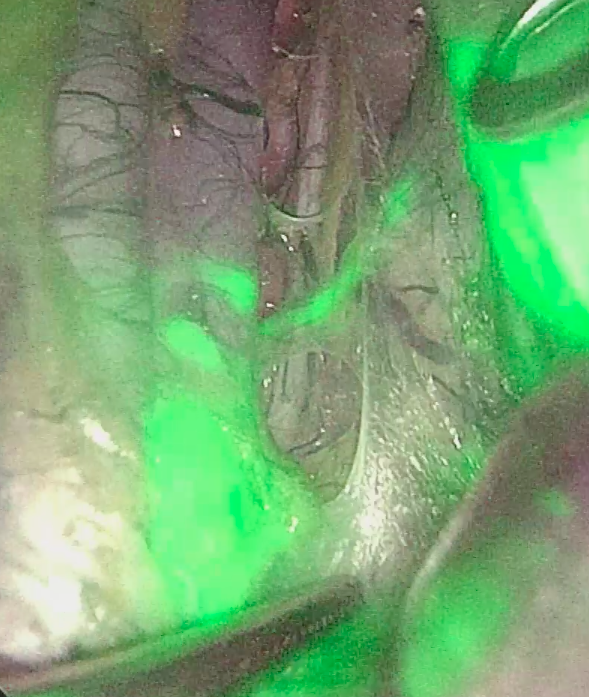

Материал и методы. В исследование включены 63 пациента с РППОК, которым в 2023–24 гг выполнена лапароскопическая правосторонняя гемиколэктомия (ЛПГКЭ) с ТМКЭ и D3-лимфодиссекцией. Всем проводили колоноскопию с подслизистым введением ICG проксимальнее и дистальнее опухоли. Доза ICG определялась эмпирически (группа 1, n=27) или индивидуально на основе площади висцерального жира (ПВЖ) по данным КТ (группа 2, n=36) – 1 мг/100 см2 ПВЖ. Успешность картирования оценивали по пятиуровневой шкале.

Результаты. Успешное картирование отмечено у 81,5 % пациентов группы 1 и у 100 % группы 2. Оптимальное картирование наблюдалось у 40,7 и 86,1 % соответственно (р<0,001). Частота осложнений составила 37,0 и 19,4 % (р=0,156), осложнения ≥III степени – 7,2 и 2,8 % (р=0,156). Медиана исследованных лимфоузлов составила 46 и 53 (р=0,054), пораженных – 3 и 4 (р=0,992).

Заключение. Индивидуальный расчет дозы ICG на основе ПВЖ целесообразен для достижения максимальной частоты успешного (100 %) и оптимального (86,1 %) картирования лимфатического коллектора при РПОК.